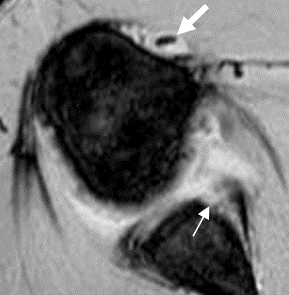

Fig 66 B. Lesión de Bankart óseo.

RM axial en FFE T2. Fractura de la glenoides anterior, por lesión de Bankart óseo. (Flecha delgada). Adicionalmente hay signos de tenosinovitis de la cabeza larga del bíceps (Flecha gruesa) y signos de sinovitis.